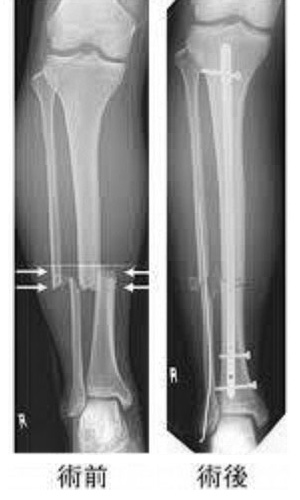

下腿骨骨折通称DXA装置といいます。腰椎及び大腿骨から、骨の強さ(骨密度)を測定します。